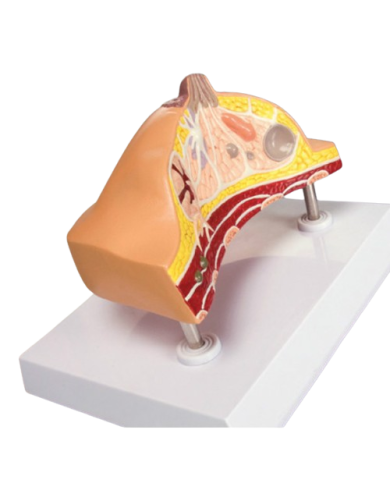

Modello anatomico PER FORNITURE CASE FARMACEUTICHE

Modello anatomico PER FORNITURE CASE FARMACEUTICHE

Modello anatomico PER FORNITURE CASE FARMACEUTICHE

Modello anatomico PER FORNITURE CASE FARMACEUTICHE

Modello anatomico PER FORNITURE CASE FARMACEUTICHE

Modello anatomico PER FORNITURE CASE FARMACEUTICHE

Modello anatomico PER FORNITURE CASE FARMACEUTICHE

Modello anatomico PER FORNITURE CASE FARMACEUTICHE

Modello anatomico PER FORNITURE CASE FARMACEUTICHE

Modello anatomico PER FORNITURE CASE FARMACEUTICHE

Modello anatomico PER FORNITURE CASE FARMACEUTICHE

Modello anatomico PER FORNITURE CASE FARMACEUTICHE

Modello anatomico PER FORNITURE CASE FARMACEUTICHE

Modello anatomico PER FORNITURE CASE FARMACEUTICHE

Modello anatomico PER FORNITURE CASE FARMACEUTICHE

Modello anatomico PER FORNITURE CASE FARMACEUTICHE

Modello anatomico PER FORNITURE CASE FARMACEUTICHE

Modello anatomico PER FORNITURE CASE FARMACEUTICHE

Modello anatomico PER FORNITURE CASE FARMACEUTICHE

Modello anatomico PER FORNITURE CASE FARMACEUTICHE

Modello anatomico PER FORNITURE CASE FARMACEUTICHE

Modello anatomico PER FORNITURE CASE FARMACEUTICHE